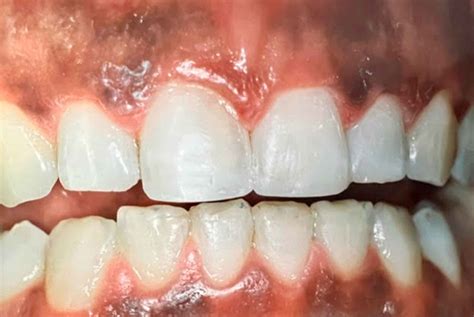

Las encías son el tejido mucoso que rodea la cavidad oral y que abarca todos los dientes. El aspecto habitual de la encía se corresponde con un color rosado, carnoso y brillante. La apariencia natural debe ser de un rosa pálido, esto indica que hay una buena circulación y que tu salud bucal es correcta. Su tejido duro, fibroso y sensible sirve de unión entre los dientes y el hueso alveolar, por lo que su buen estado de salud es fundamental para dar soporte a las piezas dentales.

Sin embargo, al igual que sucede con la coloración de la piel, hay que personas que pueden tener una encía de tonos marrones u oscuros. Si detectas que ese rosa se ha oscurecido o está acompañado de manchas negras es importante que un profesional estudie qué puede estar ocurriendo. El color y la apariencia de las encías son un indicador de su estado de salud. Su aspecto y coloración pueden sufrir alteraciones pero no debes alarmarte ya que en su mayor parte no están motivadas por patologías orales.

Las encías sanas suelen ser de un tono rosado, pero en algunos casos, pueden oscurecerse y volverse de un color negro o marrón. Este cambio puede preocupar a muchas personas, no solo por razones estéticas, sino también por la posibilidad de que sea un síntoma de algún problema de salud.